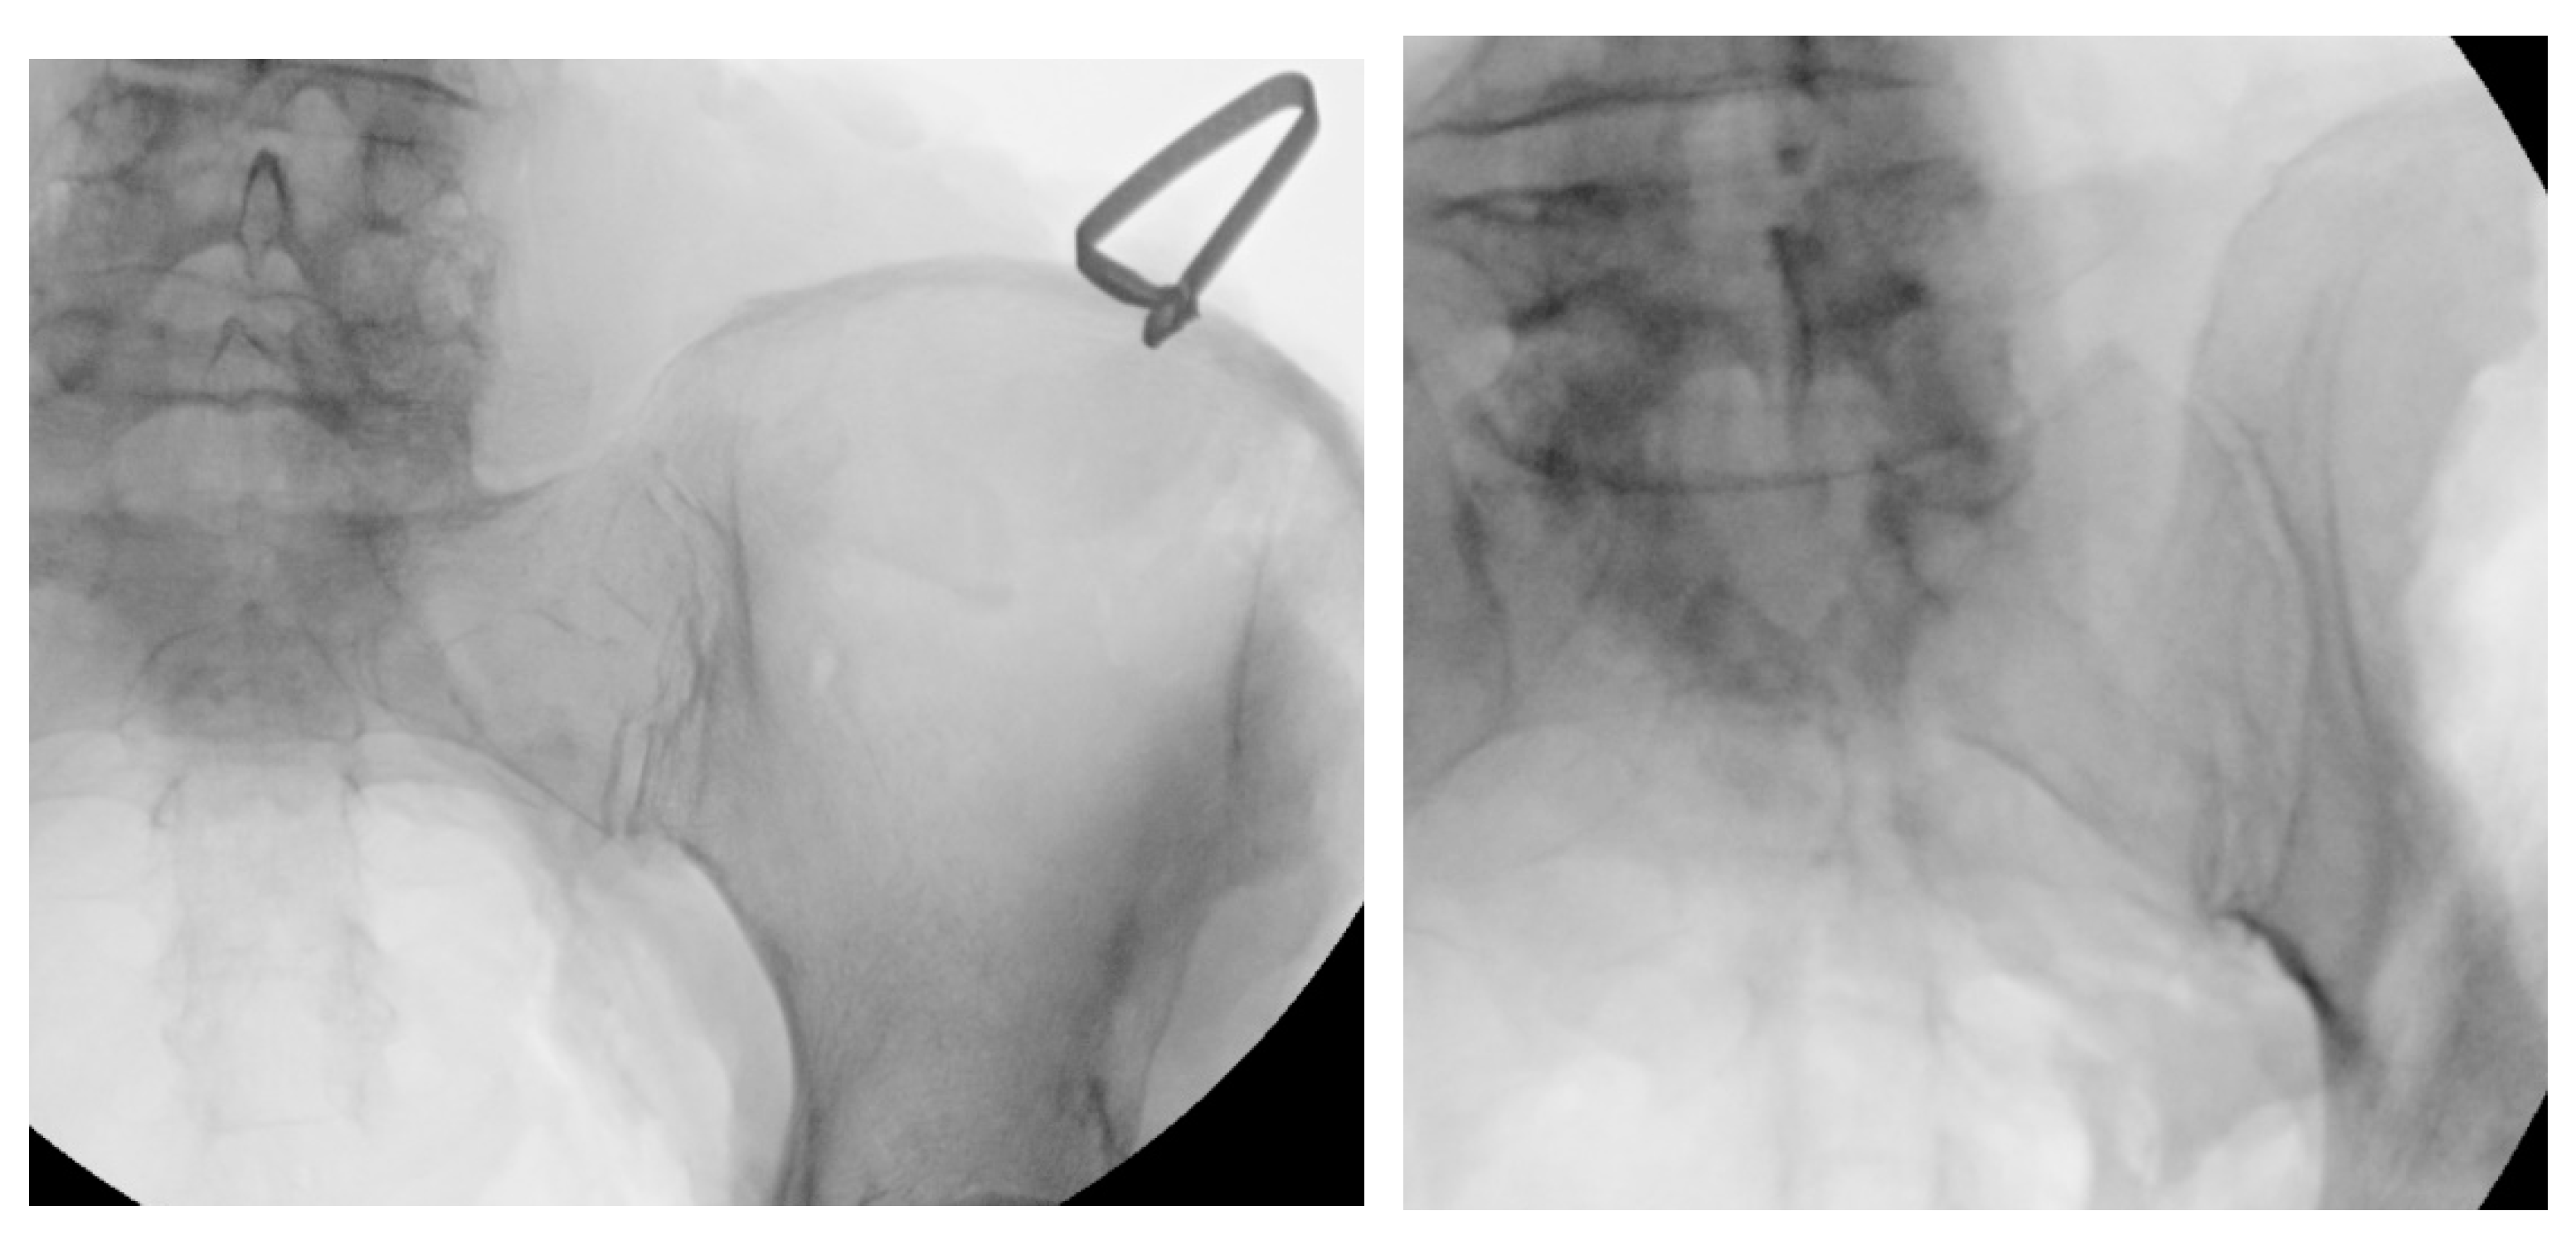

Figure 6. Oblique (left), and lateral (right) fluoroscopic views are used to confirm docking washer placement, to direct instrumentation and implantation above the sciatic notch.

The Docking Washer should be introduced over the Initial Dilator and, using inlet and outlet views, should be advanced with a trajectory that allows for transfixation of the joint space by checking the angle of the approach (Figure 6). To ensure safety, with an inlet view, the ventral aspect of the docking tangs should be observed to have adequate room on the ventral aspect of the joint (Figure 6). Finally, using a lateral view, the Impact Cap should be attached and advanced using a mallet until the base of the Washer Tower is seated against the ilium (Figure 6). To complete this step, the Impact Cap, Initial Dilator and Steinmann pin should be removed, leaving the Docking Washer Tower in place.